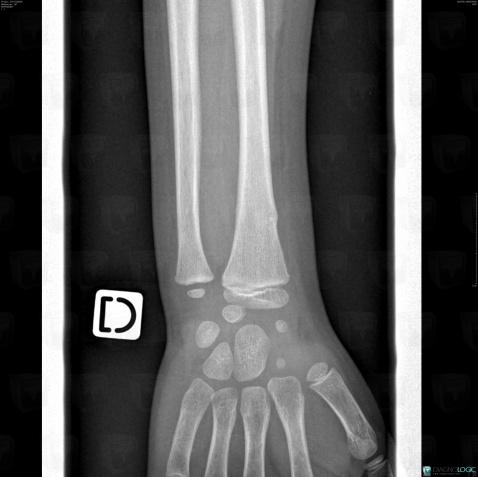

Fracture, Radius - Distal part, X rays

Here is the specific information in the key image above:

- Diagnosis Fracture, Location(s) Radius - Distal part, with gamuts